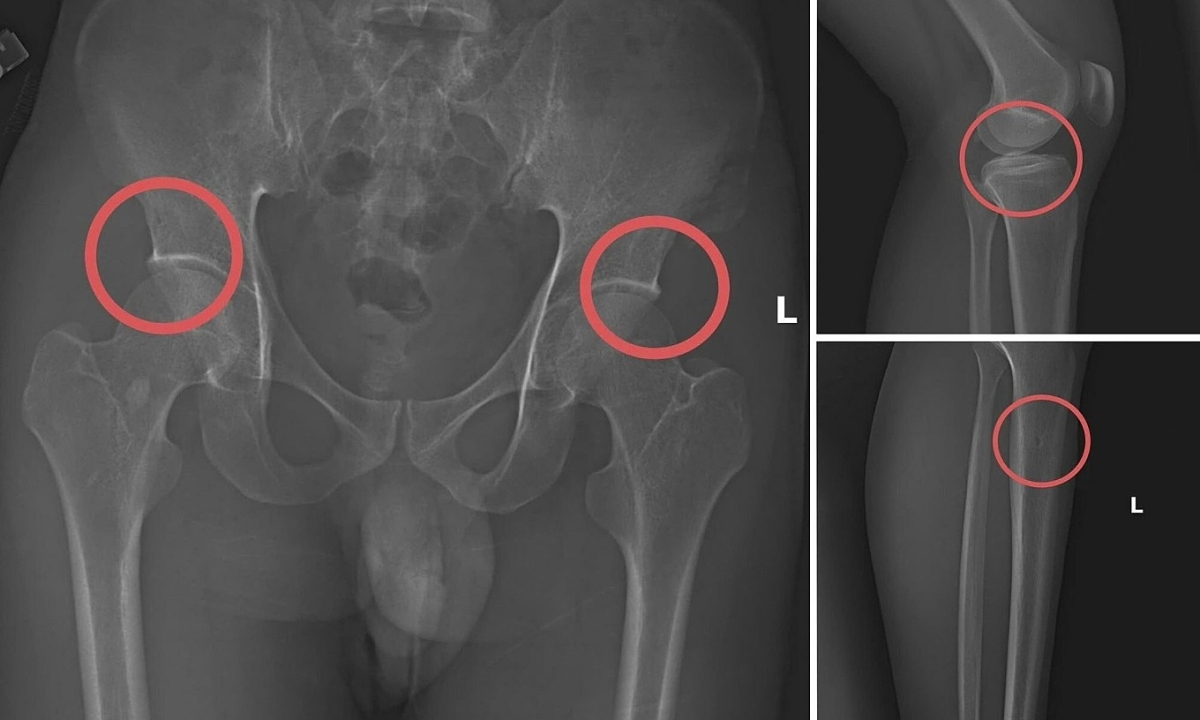

Tại đây, anh ta tiêm thuốc mê vào tĩnh mạch tay phải của người mua bảo hiểm để họ hôn mê. Sau đó, Châu dùng búa và kim tiêm đục, đâm vào vùng cơ thể đã thống nhất từ trước để tạo vết tổn thương trên xương cho nứt, vỡ. Thông thường, Châu sẽ làm rạn nứt, vỡ vùng xương chậu, đùi.

Khoảng 30 phút sau, các "chủ nhân bảo hiểm" sẽ tỉnh lại. Châu hướng dẫn họ tạo ra các vụ tai nạn "hết sức tự nhiên" như bị điện giật ngã làm gãy xương chậu, đi suối ngã gãy chân. Tiếp đến, họ gọi nhờ người đưa đến Trung tâm y tế, bệnh viện khám và điều trị để lấy bệnh án.